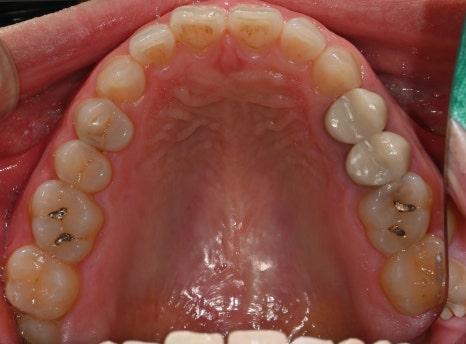

두 번째 사진: 초진 시 촬영한 상악(윗니) 어금니 사진입니다. 충치 부위와 깨진 치아 상태가 확인됩니다.